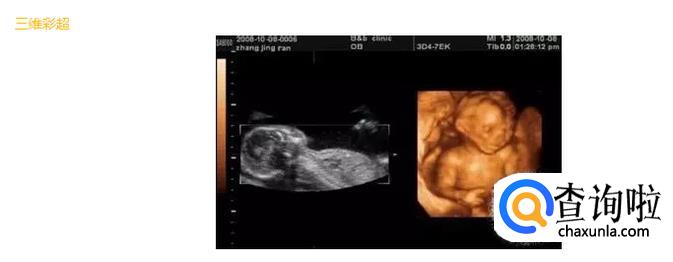

三维彩超就是将二维图像通过一个特殊的探头进行三维图像合成,透过屏幕可从各个方位观察胎宝宝。